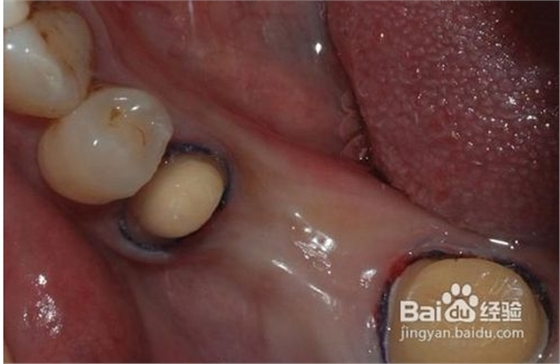

1、磨牙

為了使完成后的烤瓷牙冠戴入后不超過原始狀態(tài)的外牙厚度,一般做烤瓷牙要磨除部分自然牙。另外為了使假牙順利就位并獲得良好的固位,要將基牙制備成一定的形狀?;乐苽涞暮脡?,關(guān)系到假牙是否容易戴入以及牢固性。

4、試戴粘接

大約1周后制作的烤瓷牙即可完成。首先經(jīng)過試戴,檢查肩臺的密貼性,即冠邊緣適合性要符合標(biāo)準(zhǔn),顏色是否一致,形態(tài)是否美觀,以及鄰接關(guān)系,咬合關(guān)系等。如果確認(rèn)沒有問題,醫(yī)生通過特殊粘接劑,粘接在預(yù)修復(fù)的牙體上,烤瓷牙的修復(fù)工作全部

完成。